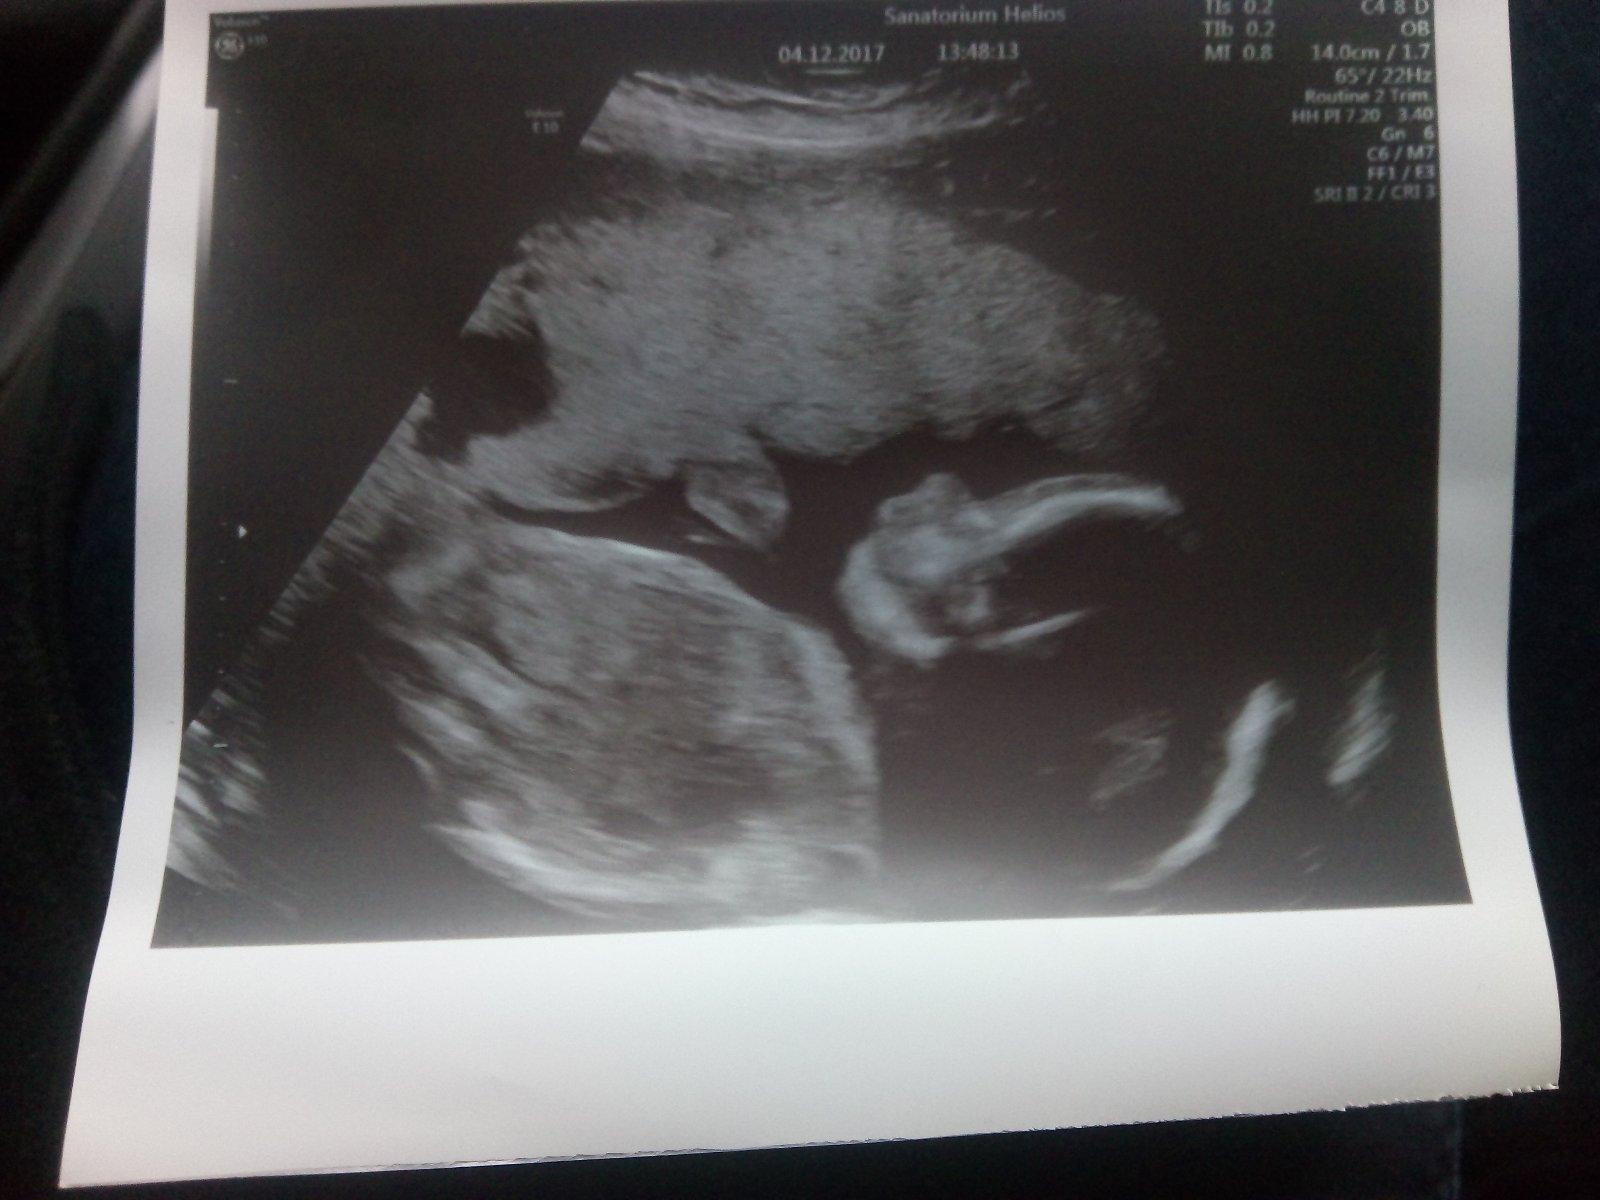

Maximálně doporučuji. Máme 8 měsíčního Kubíčka na první pokus tam a 6 mržáčků..Ostrava katastrofa!